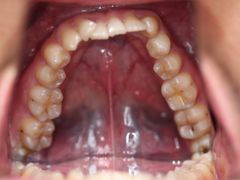

• -德伦口腔

宣有爱 | 19-05-25

报错